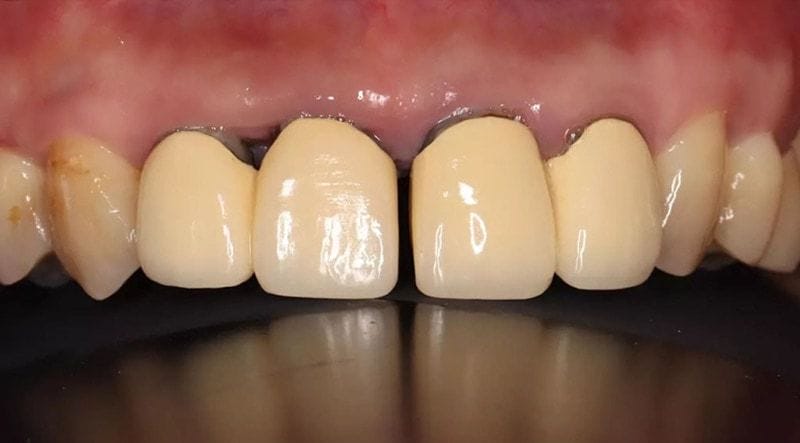

圖示:因後牙缺牙,造成Mr.Lin前牙假牙產生病理性位移

看了新竹 Mr. Lin 嚴重牙周病治療的故事,我也順便提醒大家,在我的門診中,很多牙周病患者會表示以前年輕時都沒有牙縫也沒有暴牙,現在卻有門牙縫。類似下圖中前牙門牙產生縫隙的狀況,其實是身體發出的訊號與徵兆,很多是因為後牙咬合崩壞,導致前牙病理性位移的結果。這是嚴重牙周病的重要症狀及警訊,強烈建議盡快給牙周專科醫師檢查評估!

圖示:嚴重牙周病後牙缺牙咬合崩壞,會使前牙歪斜產生縫隙(病理性位移)